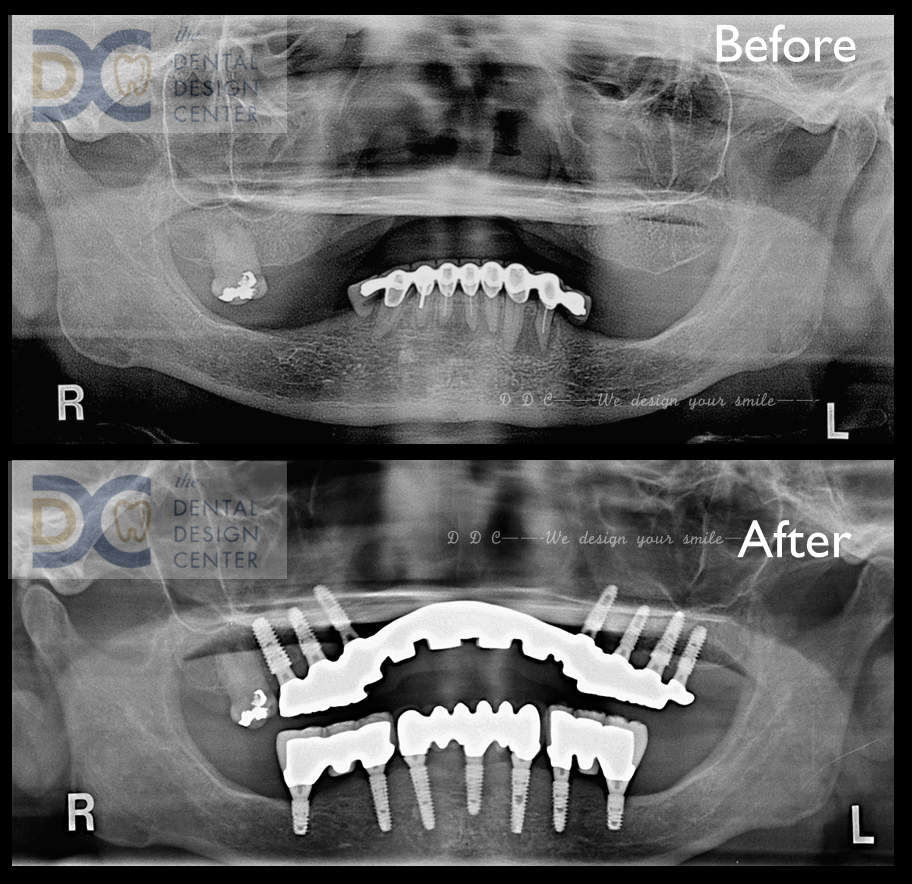

Initial OPG x-ray and intra-oral picture show a failed mandibular natural teeth bridge.

Due to the severely resorbed ridge, implants were placed in the posterior maxilla.